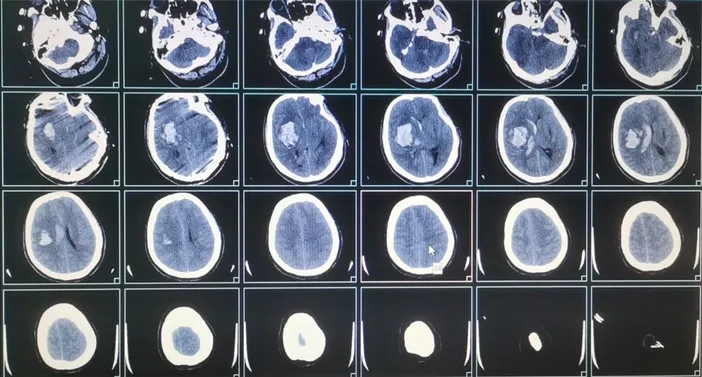

27歲的小唐凌晨上廁所時(shí)無明顯誘因突發(fā)意識(shí)不清,當(dāng)時(shí)呼之不應(yīng),口吐白沫,家屬急撥120送至我院急診。急診搶救室醫(yī)護(hù)團(tuán)隊(duì)立即對小唐完善常規(guī)抽血化驗(yàn)及影像學(xué)檢查,頭顱CT顯示右側(cè)基底節(jié)區(qū)血腫破入腦室,蛛網(wǎng)膜下腔出血,且患者血壓極高/174mmHg。

急診醫(yī)生立即邀請??茣?huì)診,神經(jīng)外二科主任施宏飛預(yù)估小唐的腦出血量大約41ml,已經(jīng)嚴(yán)重壓迫了正常的腦組織,這意味著病情十分危急,隨時(shí)可能急劇惡化,甚至可能出現(xiàn)呼吸心跳驟停而死亡,必須立即行急診手術(shù)治療。

術(shù)前影像